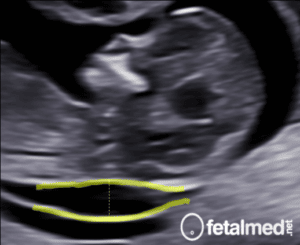

Malformação Adenomatóide Cística Tipo III (Microcística)

O prognóstico depende do tipo da malformação e da presença de hidropsia. Nos casos com hidropsia a mortalidade pode ser próxima a 100% se for tomada uma conduta expectante. A conduta será determinada pelo CVR (Cystic Adenomatoid Malformation Volume Ratio), que é calculada com dividindo-se o volume da MAC (estimado pela fórmula de volume da elipse) pela circunferência craniana:

Nos casos onde o CVR for maior que 1,6 o risco de desenvolver hidropsia é maior. Atualmente a conduta sugerida é: